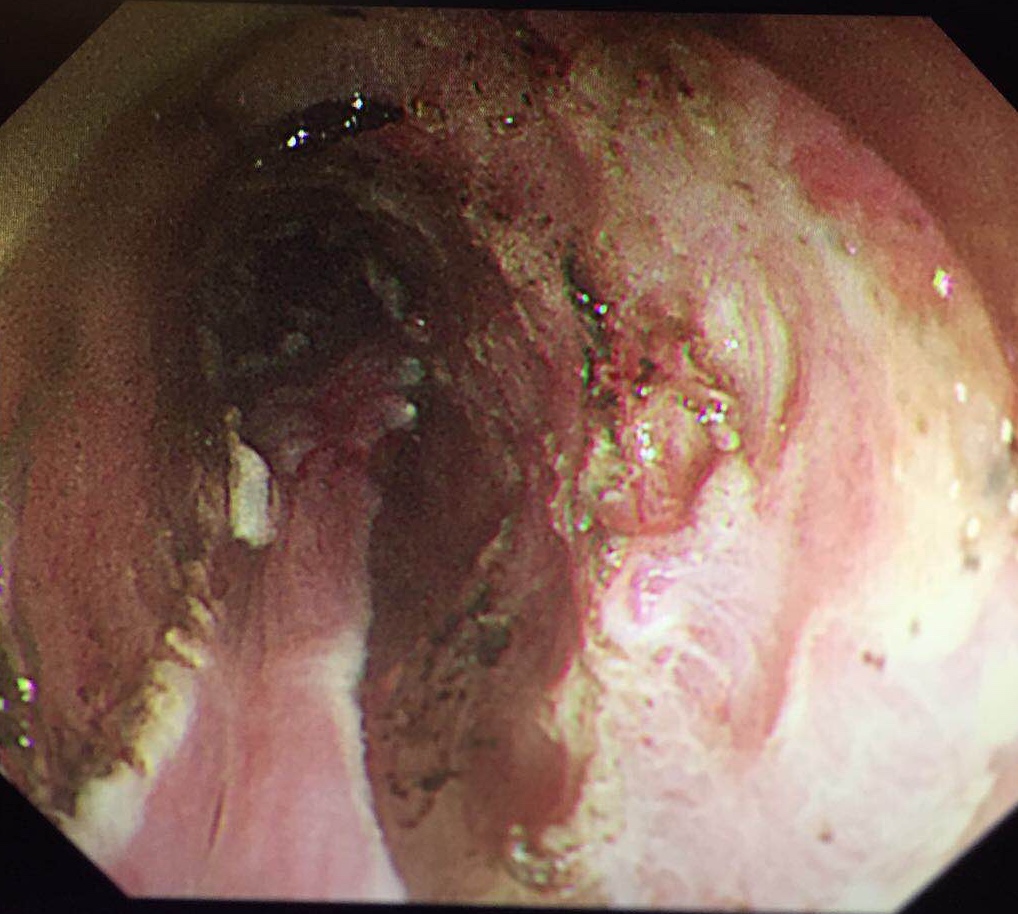

与此同时,北京协和消化疾病及消化内镜国际论坛暨第25届北京协和医院消化疾病与消化内镜研讨会在北京举行,国内外五十余位专家、五百余位代表参会。梁玮主任受邀作手术演示,完美演绎了一例病灶长达200px近环周的高难度早期食管癌“梁式ESD”治疗,向国内外同仁展示出精湛、创新的福建消化内镜技术,赢来阵阵喝彩。